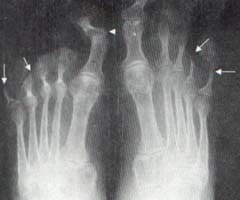

La artritis psoriásica produce alteraciones características de las articulaciones sinoviales y cartilaginosas y de las inserciones de tendones y ligamentos en el hueso. En la mayor parte de las ocasiones el diagnóstico es sencillo y se basa en sus características radiológicas específicas, entre las que se encuentra una cierta asimetría, cambios erosivos intraarticulares progresivos con separación de los bordes del hueso subcondral, proliferación perióstica, fusión ósea intraarticular y ausencia de osteoporosis en las articulaciones sinoviales; alteraciones bilaterales simétricas o asimétricas de las articulaciones sacroilíacas con osificación para vertebral; erosiones y esclerosis de las articulaciones cartilaginosas; erosiones y proliferación ósea en las zonas de inserción de tendones y ligamentos en el hueso y, por último, osteólisis de las falanges terminales. (Figura 11)

Figura 11. Pies comparativos. Se aprecian lesiones osteolíticas en las falanges distales del cuarto y quinto dedos de manera bilateral (Flechas). También hay subluxación, disminución del espacio articular y erosiones en la primera interfalángica proximal derecha (Cabeza de flecha).